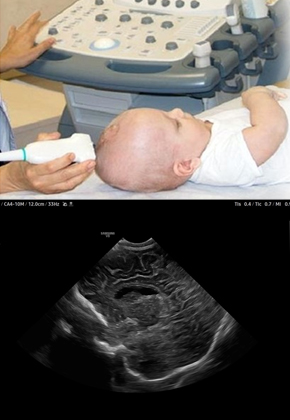

• NEUOSONOGRAM - Sonography of newborn & infant brain